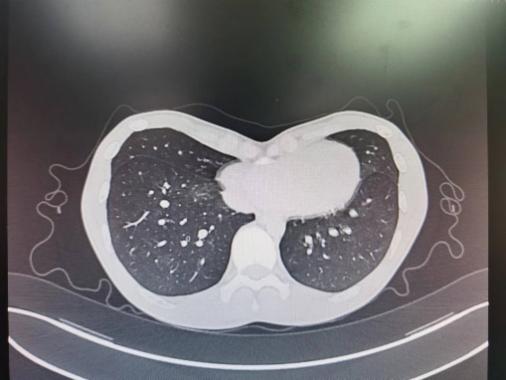

李少民教授为小高作了全面的术前检查及评估。术前胸部CT及胸廓三维重建检查显示小高的双侧胸壁基本对称,胸廓凹陷处主要位于胸骨下段,属重度凹陷畸形,凹陷的最低点恰好贴近右心室,导致心脏受压,这可能是导致小高活动后心慌、气短的原因。